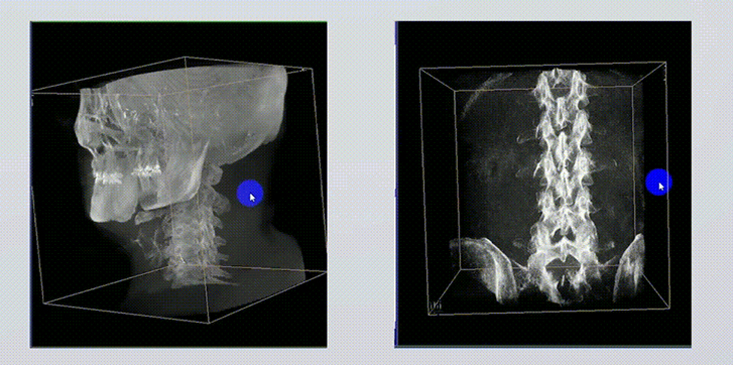

1、术中实时三维成像

术中三维成像和横断面图像提供多角度的手术诊断信息,辅助医生进行术中评估判断,诸如骨折复位情况和内植入螺钉的尺寸和位置,辅助手术更好地完成。

2、三维成像视野大

提供更大的术中三维成像视野,采集更多图像信息,可一次拍全全段颈椎、全段腰椎、七节胸椎、双侧骶髂关节、股骨头及单侧盆骨。